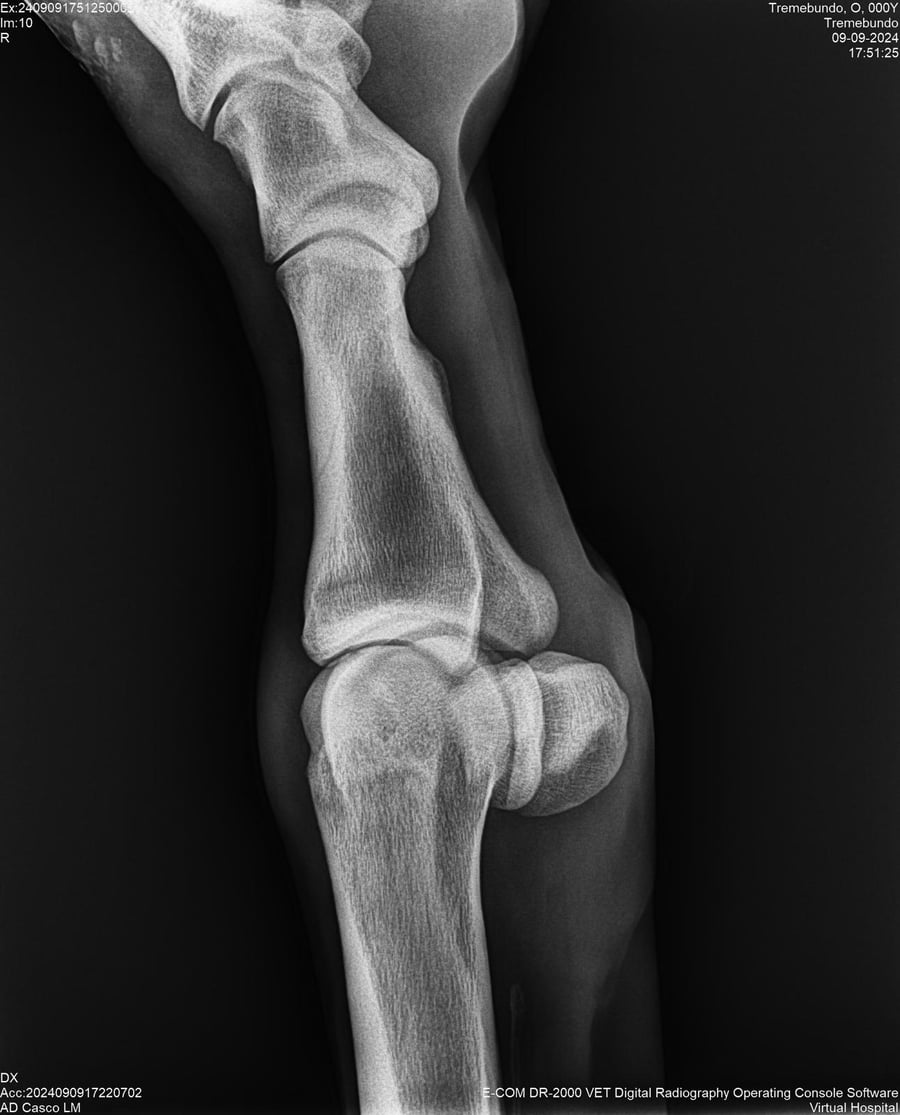

LOTE 37, TREMEBUNDO

Ficha del Lote

Identificador: #291140-

Generacion 2022